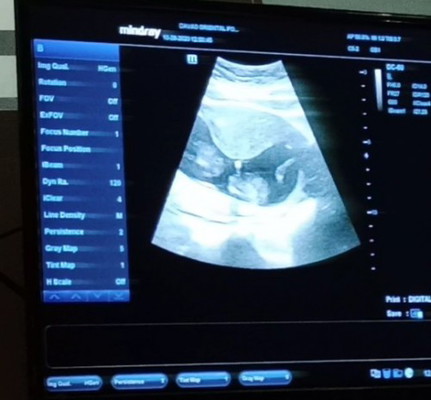

Contraction at 13 weeks

Normal lang ba magkaroon ng contraction at this early stage ng pregnancy? Medyo natakot kasi ako kahapon during my visit sa OB kasi sa ultrasound nakita na nag cocontract ang muscles ko . Binigyan nya ako pamparelax ng muscles ko for 1 week. Will this contraction be bad for the baby ? Sino naka try dito? And what did you do ? Other family members kasi are telling me na baka magka preterm labor ako because of this and natatakot ako . This is my first baby and ang tagal naming hinintay ang baby na to 😢 i'm really scared. Please assure me that everything's gonna be fine . T